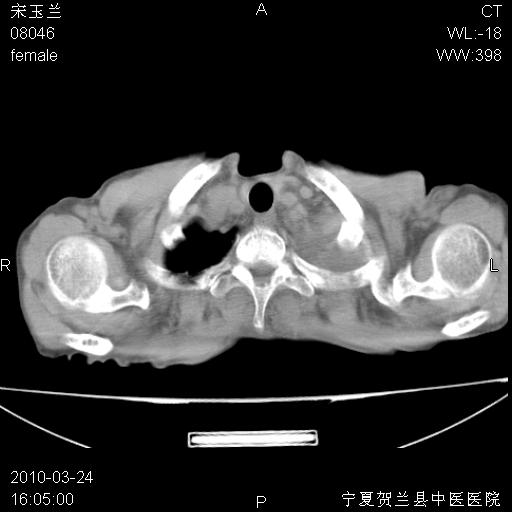

以下是引用zxl51642在2010-3-24 18:49:00的发言:[br]结合乳腺癌术后病史,考虑双肺及纵隔淋巴结多发转移、左侧胸膜转移并左侧大量胸水、左下肺膨胀不全。